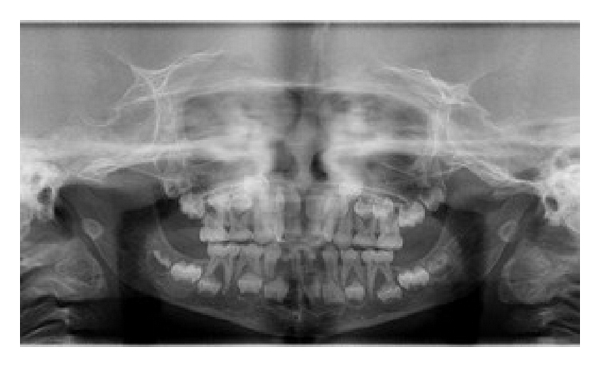

An orthopantomogram revealed absence of permanent tooth buds of permanent mandibular right and left lateral incisors and permanent mandibular right central incisor (Figure 3) and there was a generalized delay in the development of permanent tooth buds. Delayed root formation of permanent first molars was noted. No supernumerary teeth were seen in the radiograph. PA skull revealed delayed closure of fontanelle (Figure 4). CT scan of skull was done revealing focal defect in frontal bone measuring upto 3.8 cm (Figure 5).